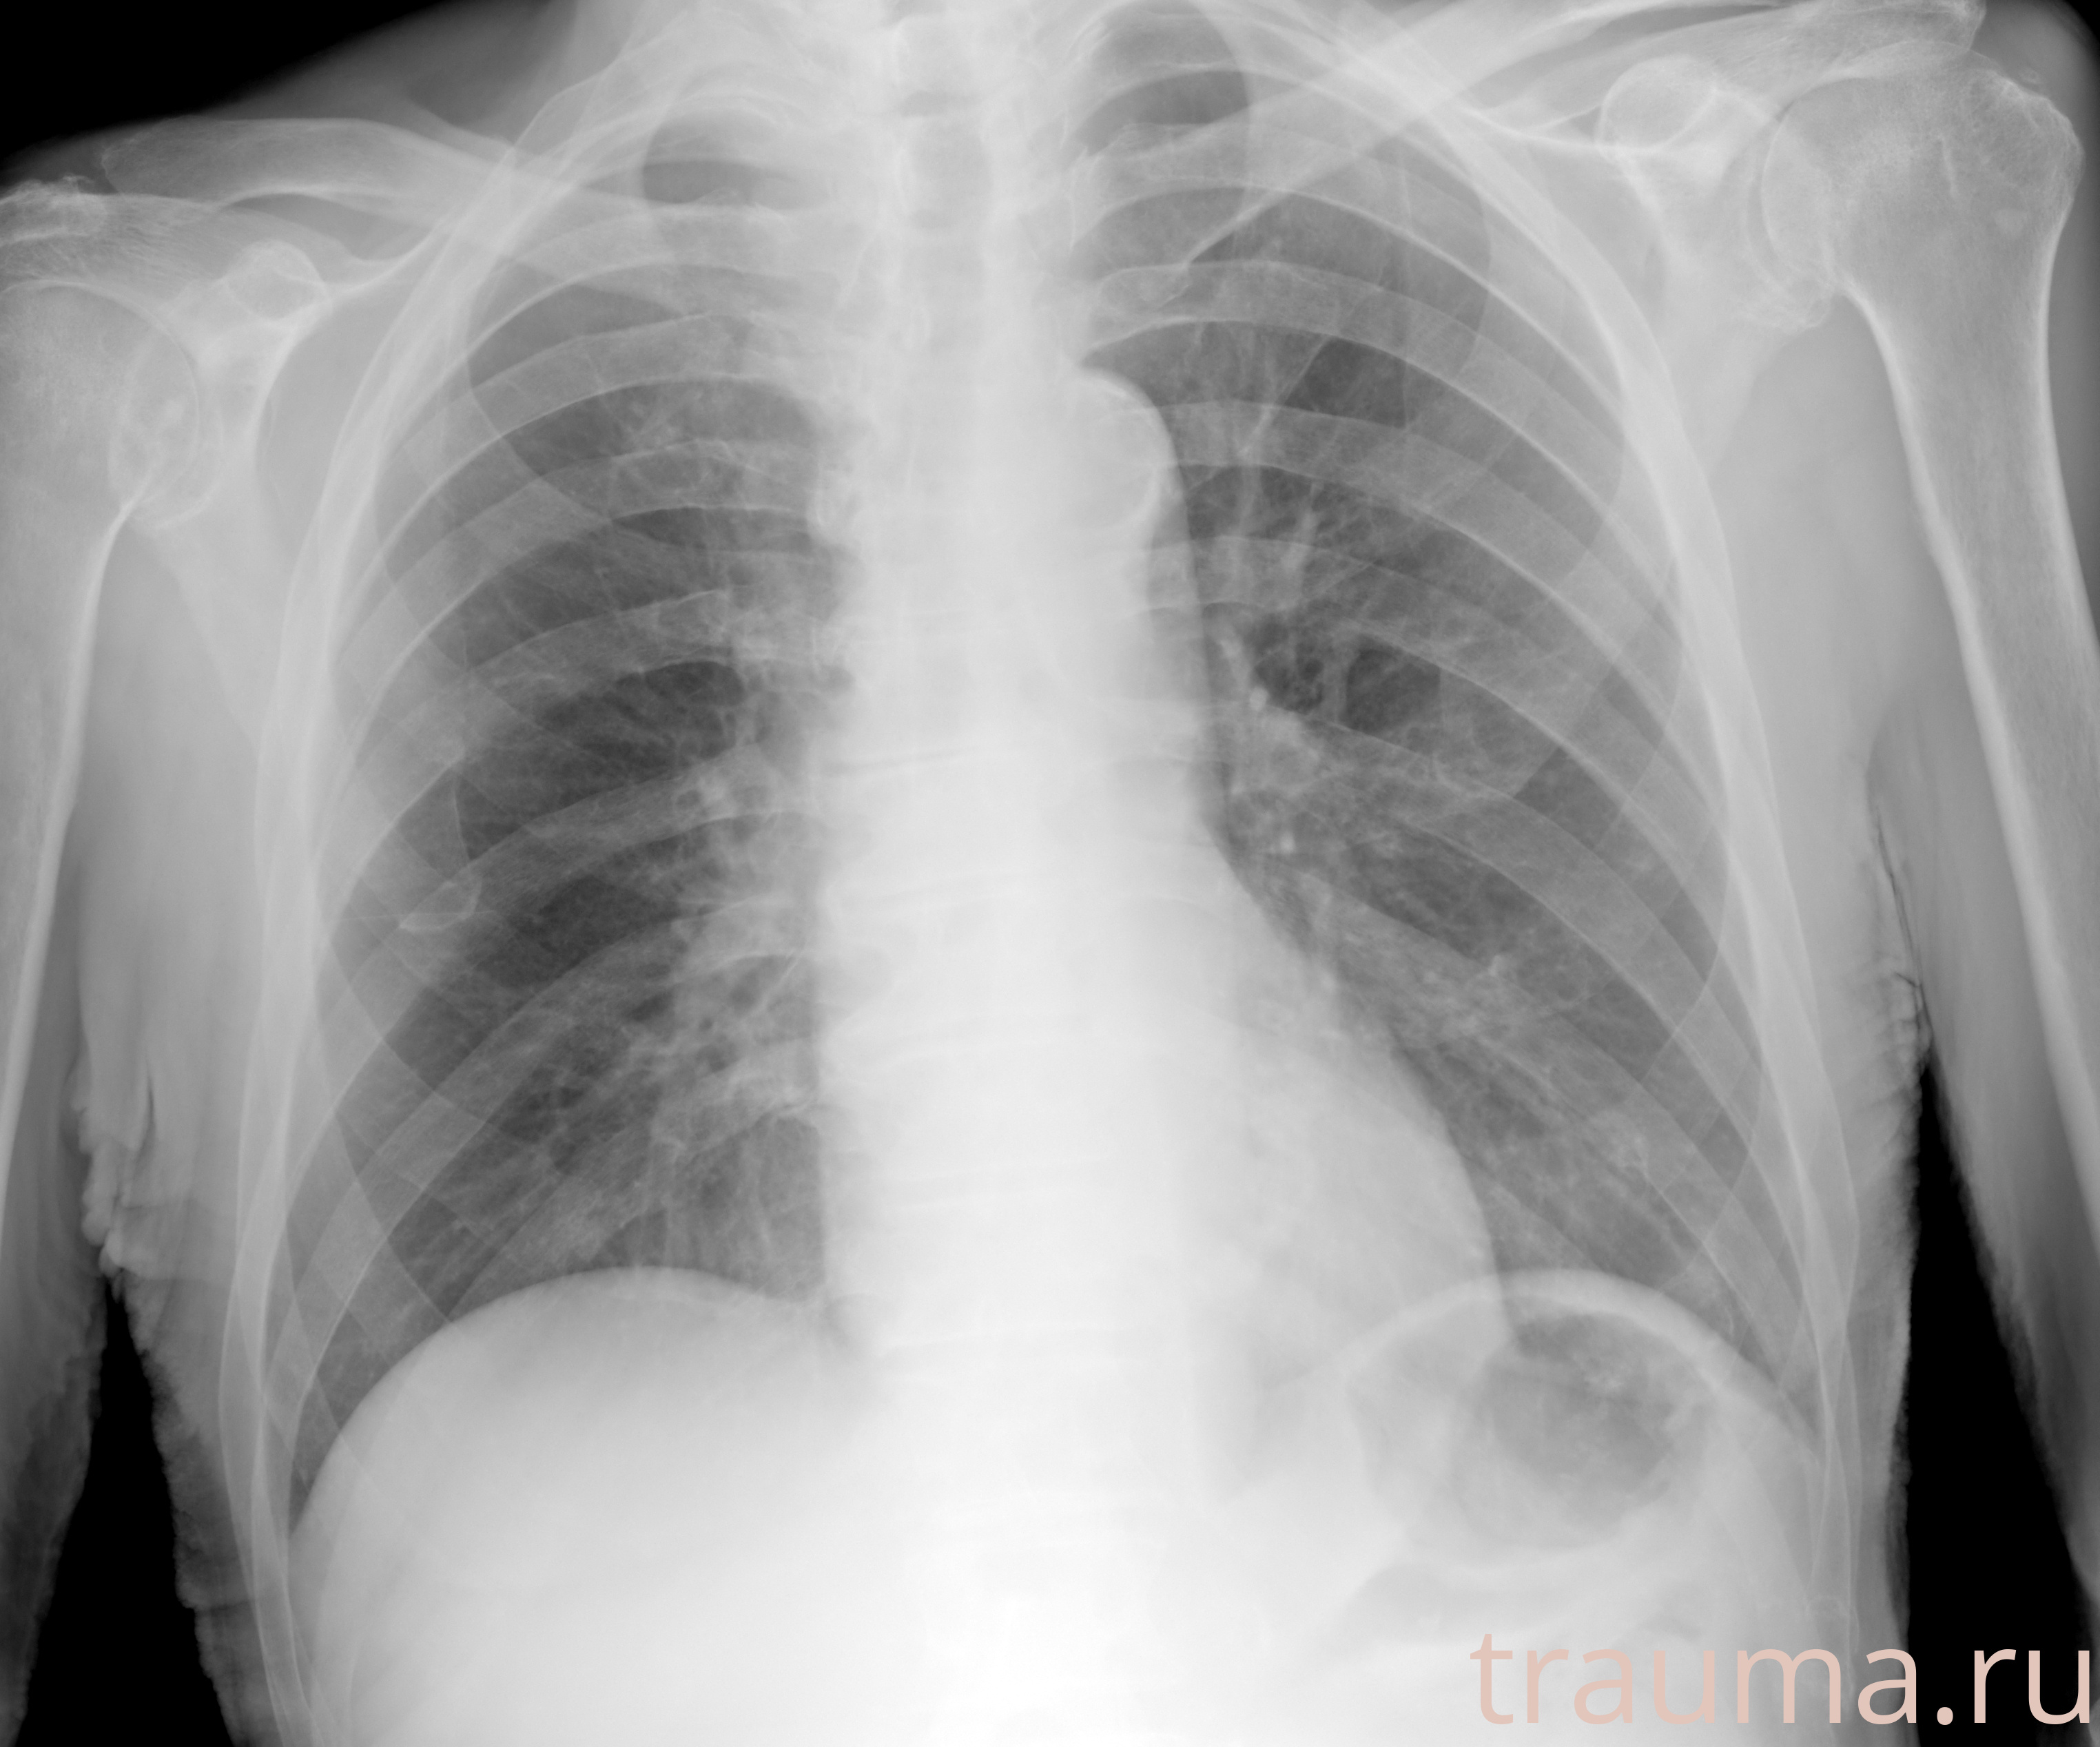

Рентгенограммы

Рентген на дому: по вашему адресу приезжает врач-рентгенолог, травматолог-ортопед с мобильным рентгеновским аппаратом, проводит диагностику травмы или заболевания, делает необходимые рентгенограммы, дает рекомендации по дальнейшему лечению. Получить качественные снимки в домашних условиях возможно благодаря уникальной методике, разработанной МосРентген Центром для института  Склифосовского

при переломе шейки бедра и пневмонии от компании МосРентген Центр - партнера Института имени Склифосовского